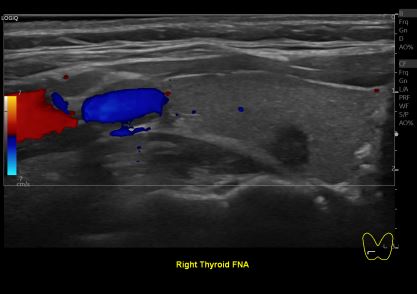

상기환자 갑상선 추적 관찰위해 내원하신 30대 여성분으로

의심스러운 갑상선 우엽 세침검사 결과 갑상선암으로 진단되었습니다.